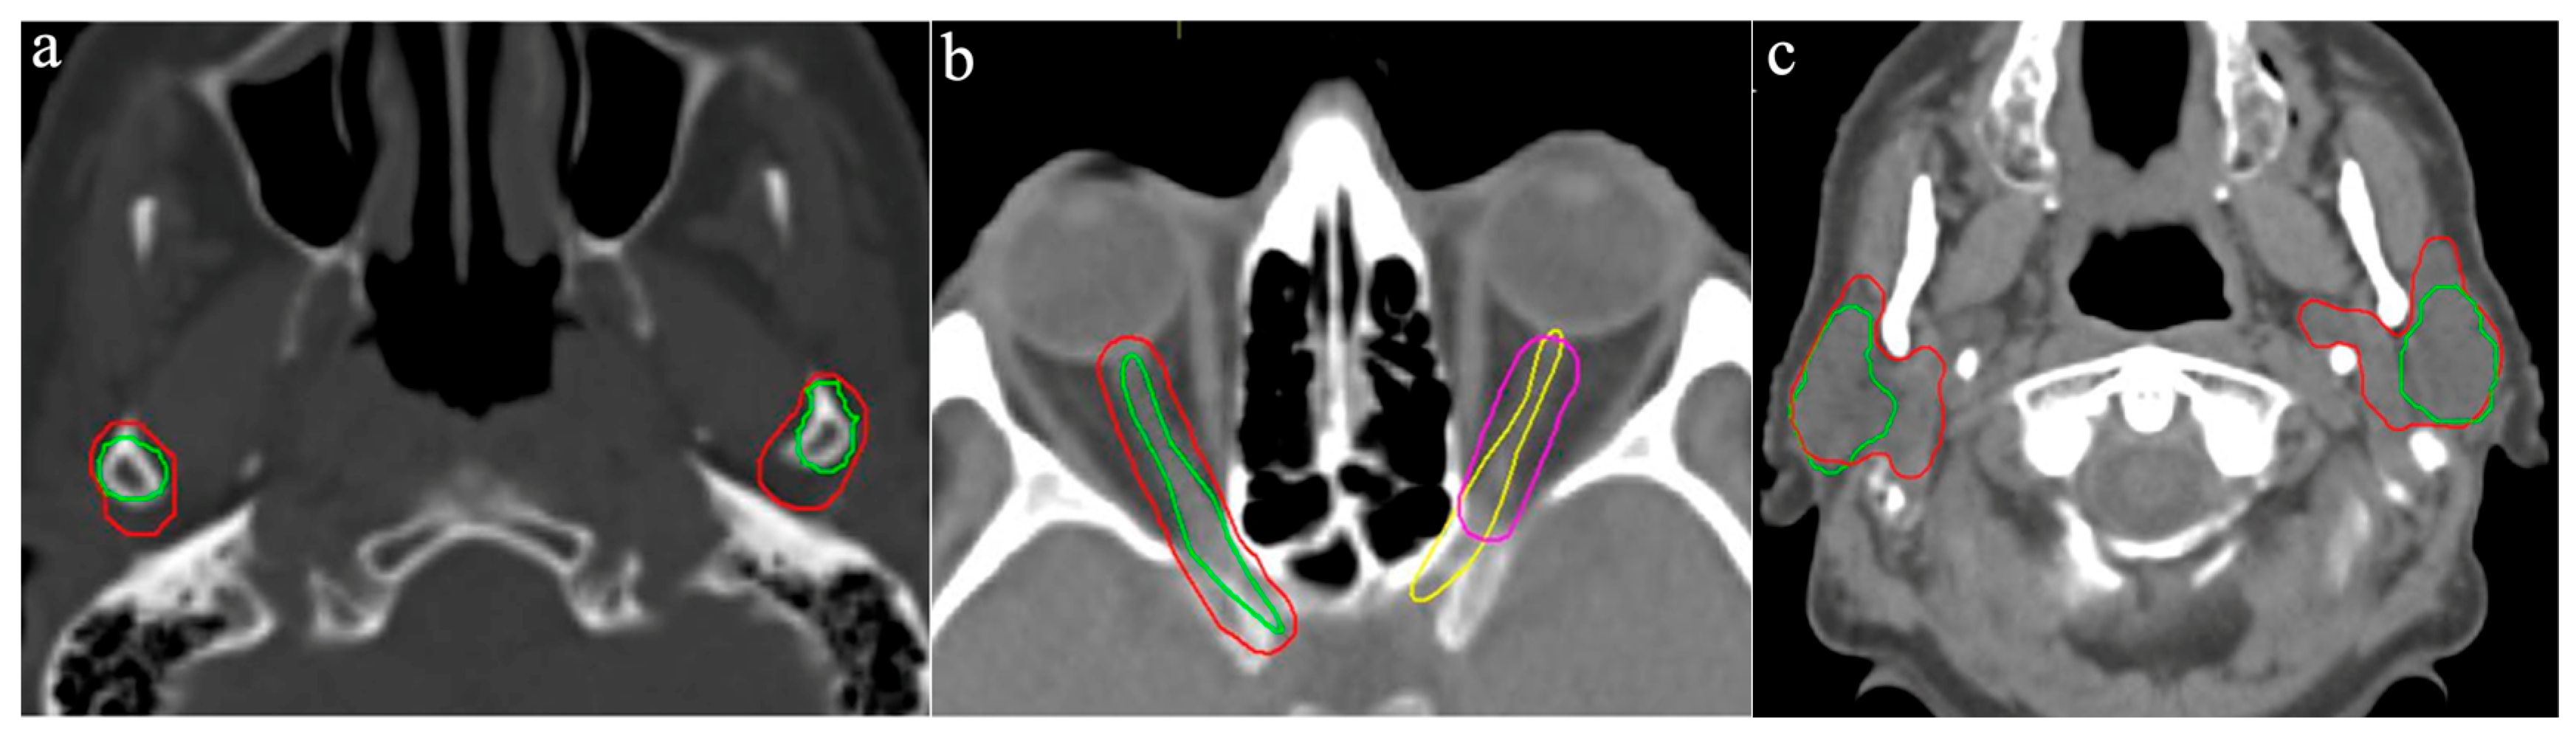

The pituitary gland was delineated by only seven ROs and exhibited the highest CoV (0.82, Range: 0.18–1.96 cm3). The largest volume resulted from cranial extension beyond the sella turcica, incorporating portions of the optic chiasm and the middle cerebral artery (Figure 2a). Conversely, the smallest volume was delineated on a single CT slice.

The left and right inner ear had a CoV of 0.72 and 0.68, respectively, with volume ranges of 0.12–2.84 cm3 and 0.11–2.38 cm3, respectively. One participant included the entire petrous part of the temporal bone, leading to the largest delineated volume, while another contoured only a small central portion of the inner ear on two CT slices (Figure 2b).

The optic chiasm was delineated by nine of the ten participants, with a mean volume of 1.80 cm3 (Range: 0.36–3.62 cm3, CoV: 0.67). Variability was primarily caused by the addition of margins to the OAR, leading to the inclusion of portions of the optic nerves and adjacent vascular structures, such as the anterior and middle cerebral arteries (Figure 2c). Four participants applied such margin to the optic chiasm measuring up to 6 mm.

Due to a broader interpretation of the inner ear as an OAR, significant variation in contouring was observed (Figure 6a,b). Typically, the cochlea is considered one of the critical OARs in this localization, defined as the bony cavity located anterior to the labyrinth and lateral to the internal auditory canal [19]. The inclusion of the entire petrous portion of the temporal bone, rather than restricting delineation to the cochlea, appears to be a frequent contributor to interobserver variability [20]. Optimal identification of the cochlea is best achieved using CT bone window settings, which may help prevent common sources of error. These include inadvertent contouring of adjacent structures such as the semicircular canals instead of the cochlea (Figure 6a), or excessive ventral extension of the contour over the petrous temporal bone into neighboring structures such as the carotid artery (Figure 6b).

Figure 2. Variation in OAR outlines: (a) Pituitary gland, (b) Left and right inner ear, (c) optic chiasm. Different colored lines represent the OAR outlines of the respective participants.

Figure 6. Variation in inner ear outlines: (a) Delineation of the semicircular canals rather than the cochlea (pink outline), (b) Contour outside the petrous part of the temporal bone. Different colored lines represent the OAR outlines of the respective participants.